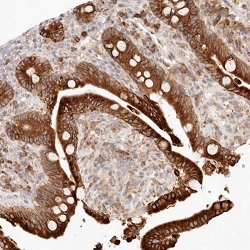

- Immunohistochemical staining of human colon with C1orf127 polyclonal antibody ( Cat # PAB27993 ) shows strong cytoplasmic positivity in glandular cells at 1:20 - 1:50 dilution.

- Immunohistochemistry (Formalin/PFA-fixed paraffin-embedded sections)